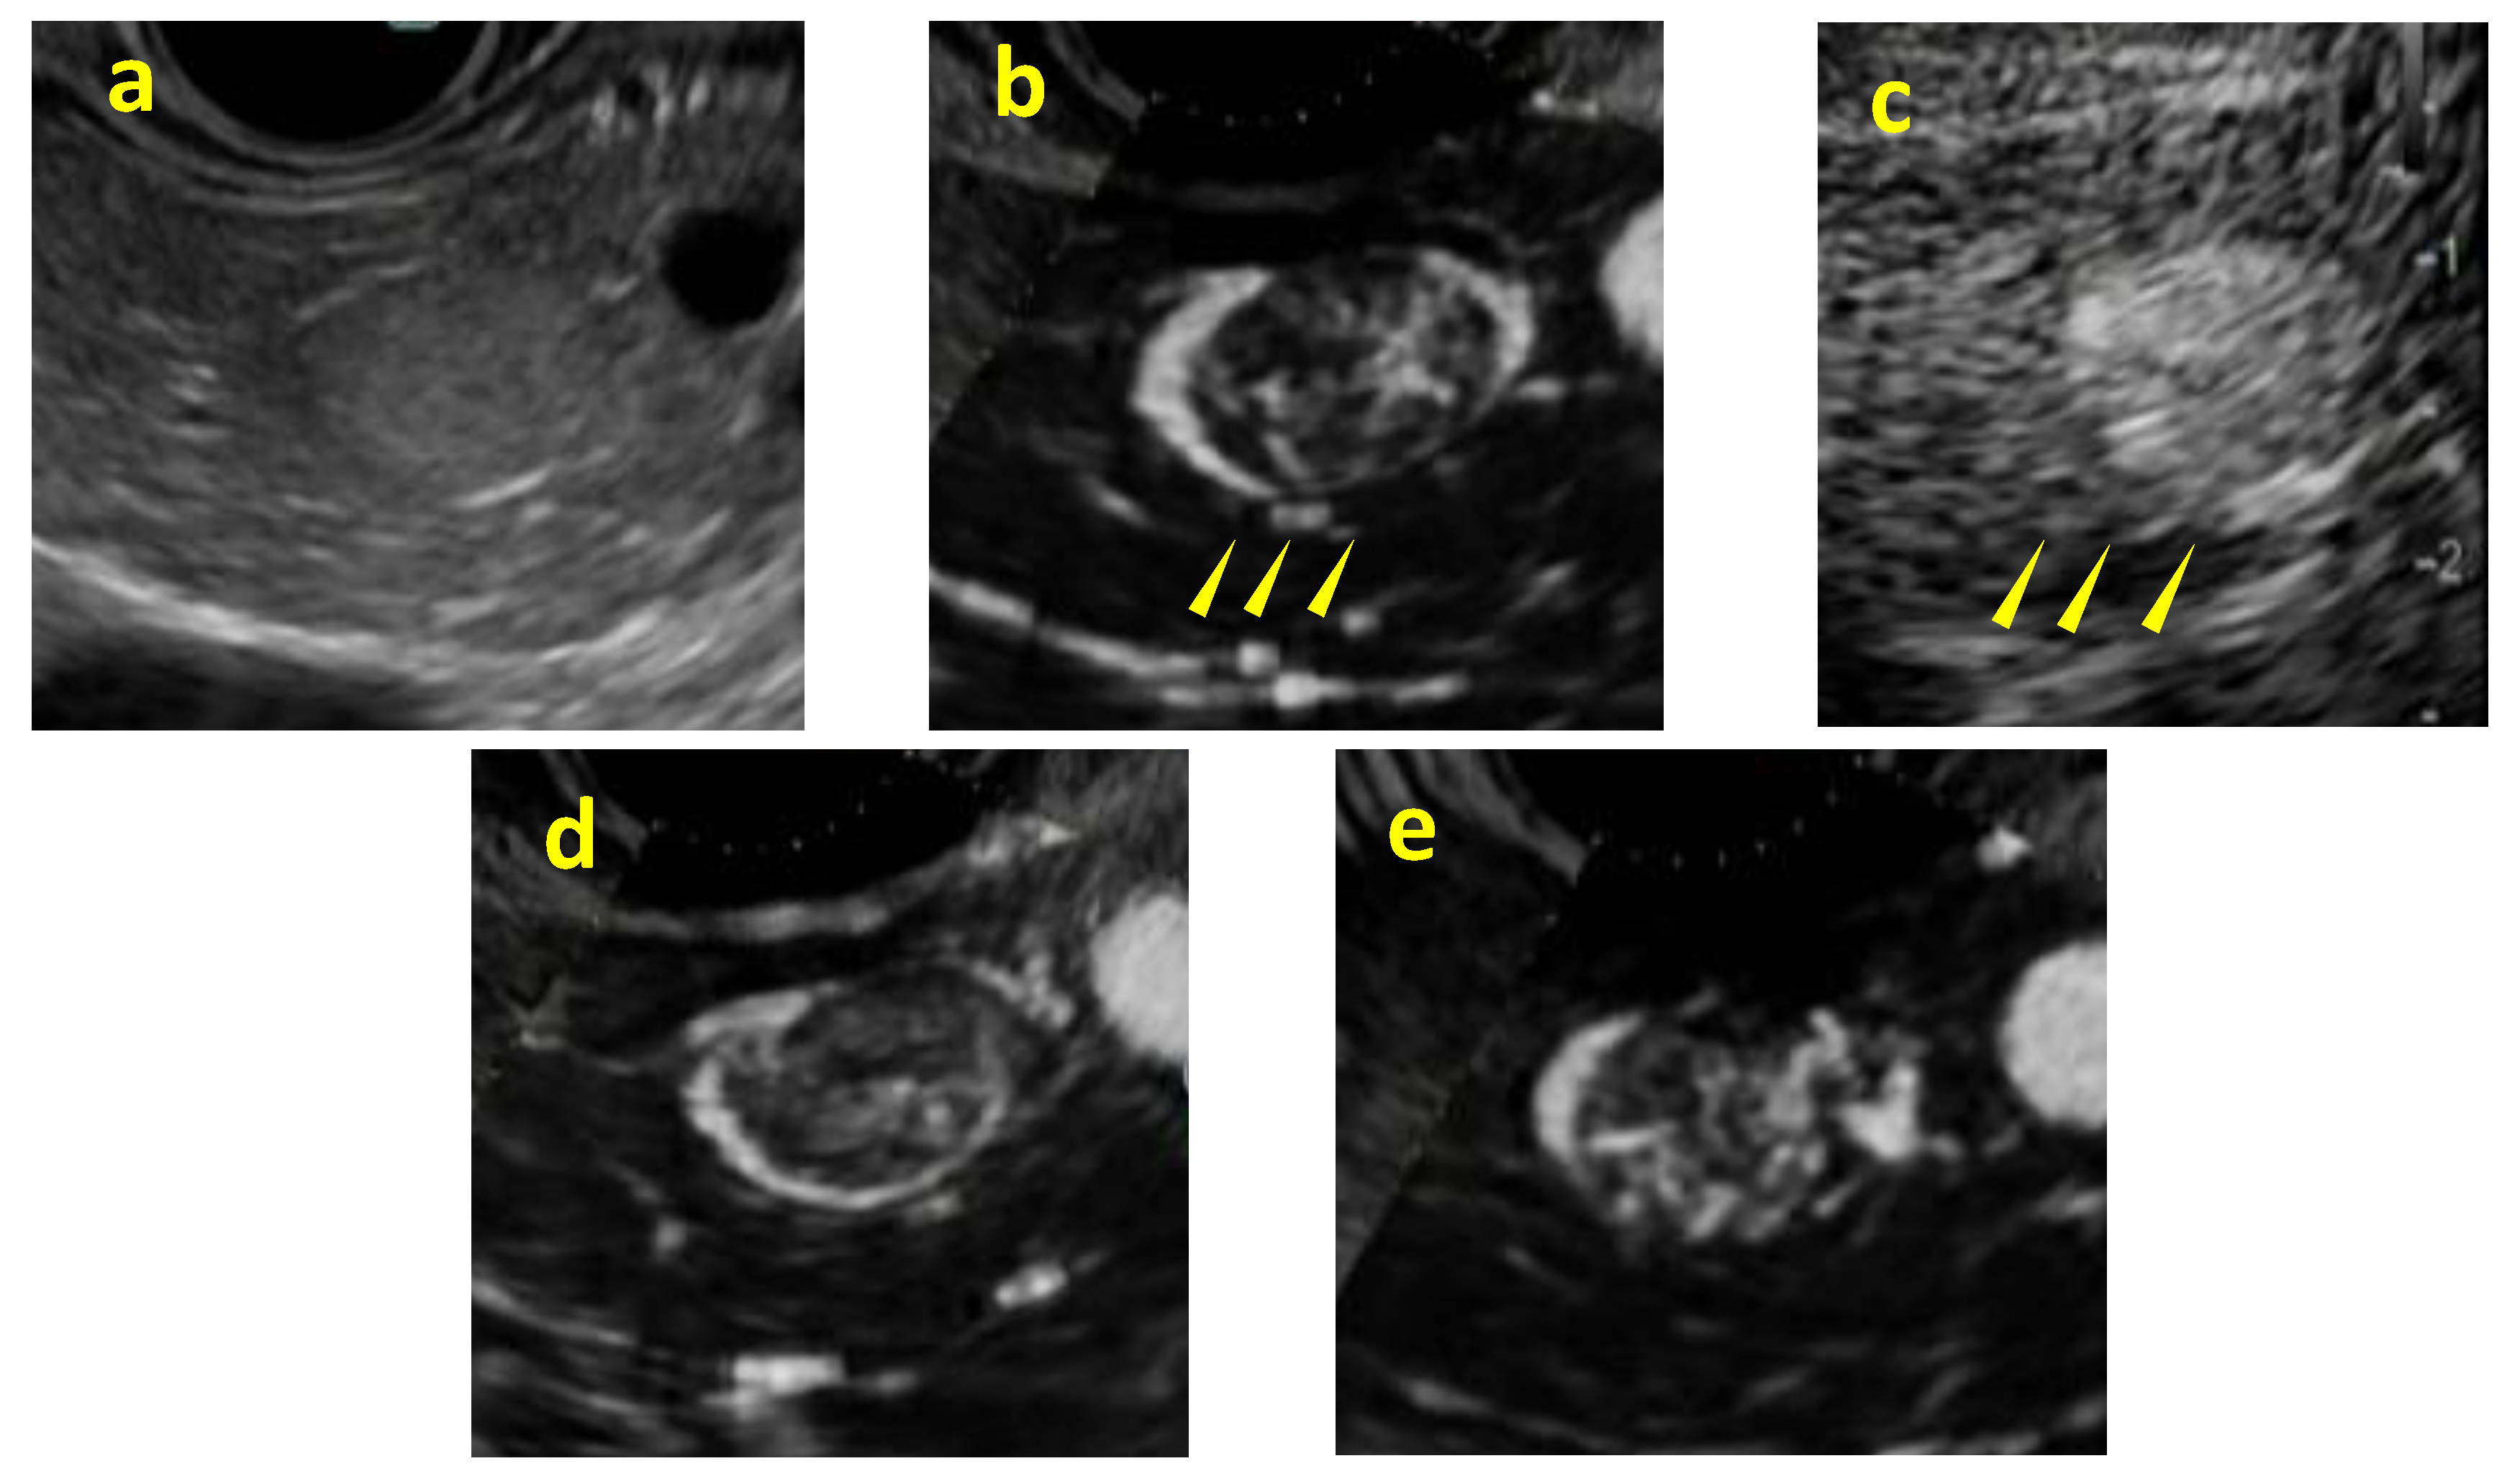

Background/Objectives: Although contrast-enhanced endoscopic ultrasound (CH-EUS) plays an important role in the ultrasound imaging-based diagnosis of intra-abdominal hypervascular tumors, detective flow imaging EUS (DFI-EUS), which can detect micro-blood flow without using a contrast agent, has recently emerged. In this study, we investigated the usefulness of DFI-EUS for detecting intra-abdominal hypervascular tumors. Methods: Thirteen patients with intra-abdominal hypervascular tumors detected on contrast-enhanced computed tomography who underwent DFI-EUS and CH-EUS were included. The lesions were classified into non-enhancement, hypo-enhancement, iso-enhancement, and hyper-enhancement patterns. Vascular structural patterns were classified as non-enhancement, homogeneous or heterogeneous enhancement. On DFI-EUS, patients who showed heterogeneous enhancement were evaluated for the presence or absence of dendritic and peritumoral capsule-like structures. Contrast patterns, vascular structure patterns, and detection capabilities of DFI-EUS and CH-EUS were examined. Results: The final diagnoses were pancreatic neuroendocrine neoplasm in 10 patients (76.9%), gastrointestinal neuroendocrine neoplasm in one patient (7.6%), gastrointestinal stromal tumor in one patient (7.6%), and metastatic pancreatic tumor in one patient (7.6%). The contrast patterns (DFI-EUS vs. CH-EUS) were non-enhancement in 7.7% vs. 0%, iso-enhancement in 15.3% vs. 23.0%, and hyper-enhancement in 76.9% vs. 76.9%. The vascular structure patterns (DFI-EUS vs. CH-EUS) showed a homogeneous enhancement of 0% vs. 100% and a heterogeneous enhancement of 92% vs. 0%. Patients with heterogeneous enhancement on DFI-EUS showed a dendritic structure in 91.6% and capsule-like structures in 75.0% of patients. Conclusions: DFI-EUS and CH-EUS showed comparable iso-enhancement or hyper-enhancement patterns. In contrast, DFI-EUS revealed the characteristic heterogeneous patterns of dendritic and capsular-like vascular structures.

- Yamashita, Y.; Yoshikawa, T.; Yamazaki, H.; Kawaji, Y.; Tamura, T.; Hatamaru, K.; Itonaga, M.; Ashida, R.; Ida, Y.; Maekita, T.; et al. A Novel Endoscopic Ultrasonography Imaging Technique for Depicting Microcirculation in Pancreatobiliary Lesions without the Need for Contrast-Enhancement: A Prospective Exploratory Study. Diagnostics (Basel) 2021, 11. [CrossRef]

- Nihei, S.; Kurita, Y.; Hasegawa, S.; Hosono, K.; Kobayashi, N.; Kubota, K.; Nakajima, A. Detective flow imaging endoscopic ultrasound for localizing pancreatic insulinomas that are undetectable with other imaging modalities. Endoscopy 2024, 56, E342-e343. [CrossRef]

- Miwa, H.; Sugimori, K.; Yonei, S.; Yoshimura, H.; Endo, K.; Oishi, R.; Funaoka, A.; Tsuchiya, H.; Kaneko, T.; Numata, K.; et al. Differential Diagnosis of Solid Pancreatic Lesions Using Detective Flow Imaging Endoscopic Ultrasonography. Diagnostics (Basel) 2024, 14. [CrossRef]

- Mulqui, M.V.; Caillol, F.; Ratone, J.P.; Hoibian, S.; Dahel, Y.; Meunier, É.; Archimbaud, C.; Giovannini, M. Detective flow imaging versus contrast-enhanced EUS in solid pancreatic lesions. Endosc Ultrasound 2024, 13, 248-252. [CrossRef]